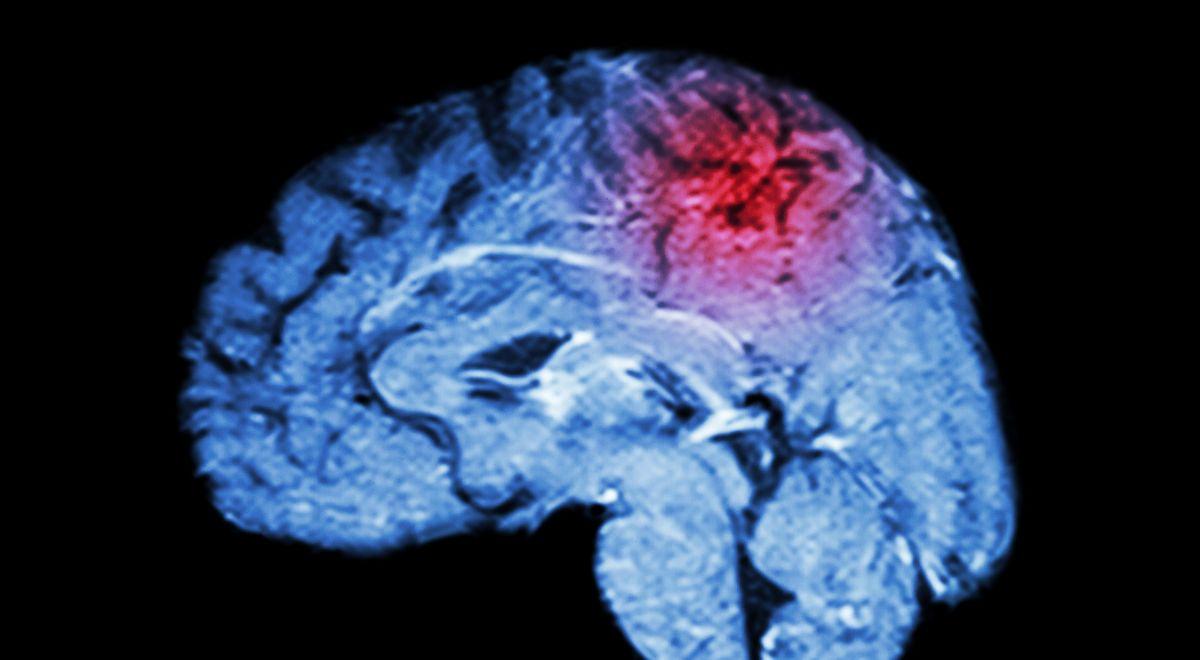

Herseninfarct

De behandeling van een herseninfarct is de afgelopen jaren ingrijpend veranderd. Dankzij intraveneuze trombolyse is de overleving sterk verbeterd, al blijft het herseninfarct in de top drie van doodsoorzaken. In deze nascholing staat de actuele stand van zaken rondom de behandeling en secundaire preventie van een TIA of herseninfarct centraal. U krijgt inzicht in recente ontwikkelingen, zoals het gebruik van clopidogrel als alternatief voor acetylsalicylzuur met dipyridamol, en van DOAC’s bij atriumfibrilleren. Ook wordt stilgestaan bij het verschuivende begrip TIA en waarom de termen ‘beroerte’ en ‘CVA’ niet langer volstaan. Naast de acute fase, komt in deze nascholing ook de cruciale rol van de apotheker aan bod in de secundaire preventie: het bewaken van contra-indicaties en interacties, het bevorderen van therapietrouw, en begeleiding bij het gebruik van DOAC’s binnen de Keten Antistolling. Verder is er aandacht voor ondersteuning bij slikproblemen, cognitieve stoornissen en valrisico’s. Tot slot bespreekt de nascholing ook de epidemiologie, symptomen en snelle herkenning van een TIA of herseninfarct – essentieel, want time is brain.